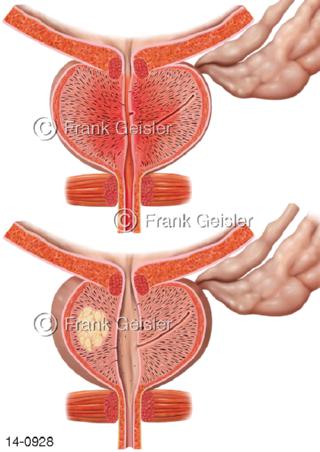

Bildergalerie Urogenitalsystem

Bilder zum Urogenitalsystem mit Urogenitalorgane, Urogenitaltrakt, zum Harn- und Geschlechtsapparat, Harnorgane und Geschlechtsorgane, Organe der Harnwege und der Fortpflanzung, Harnorgane und Geschlechtsorgane im männlichen und weiblichen Urogenitalsystem